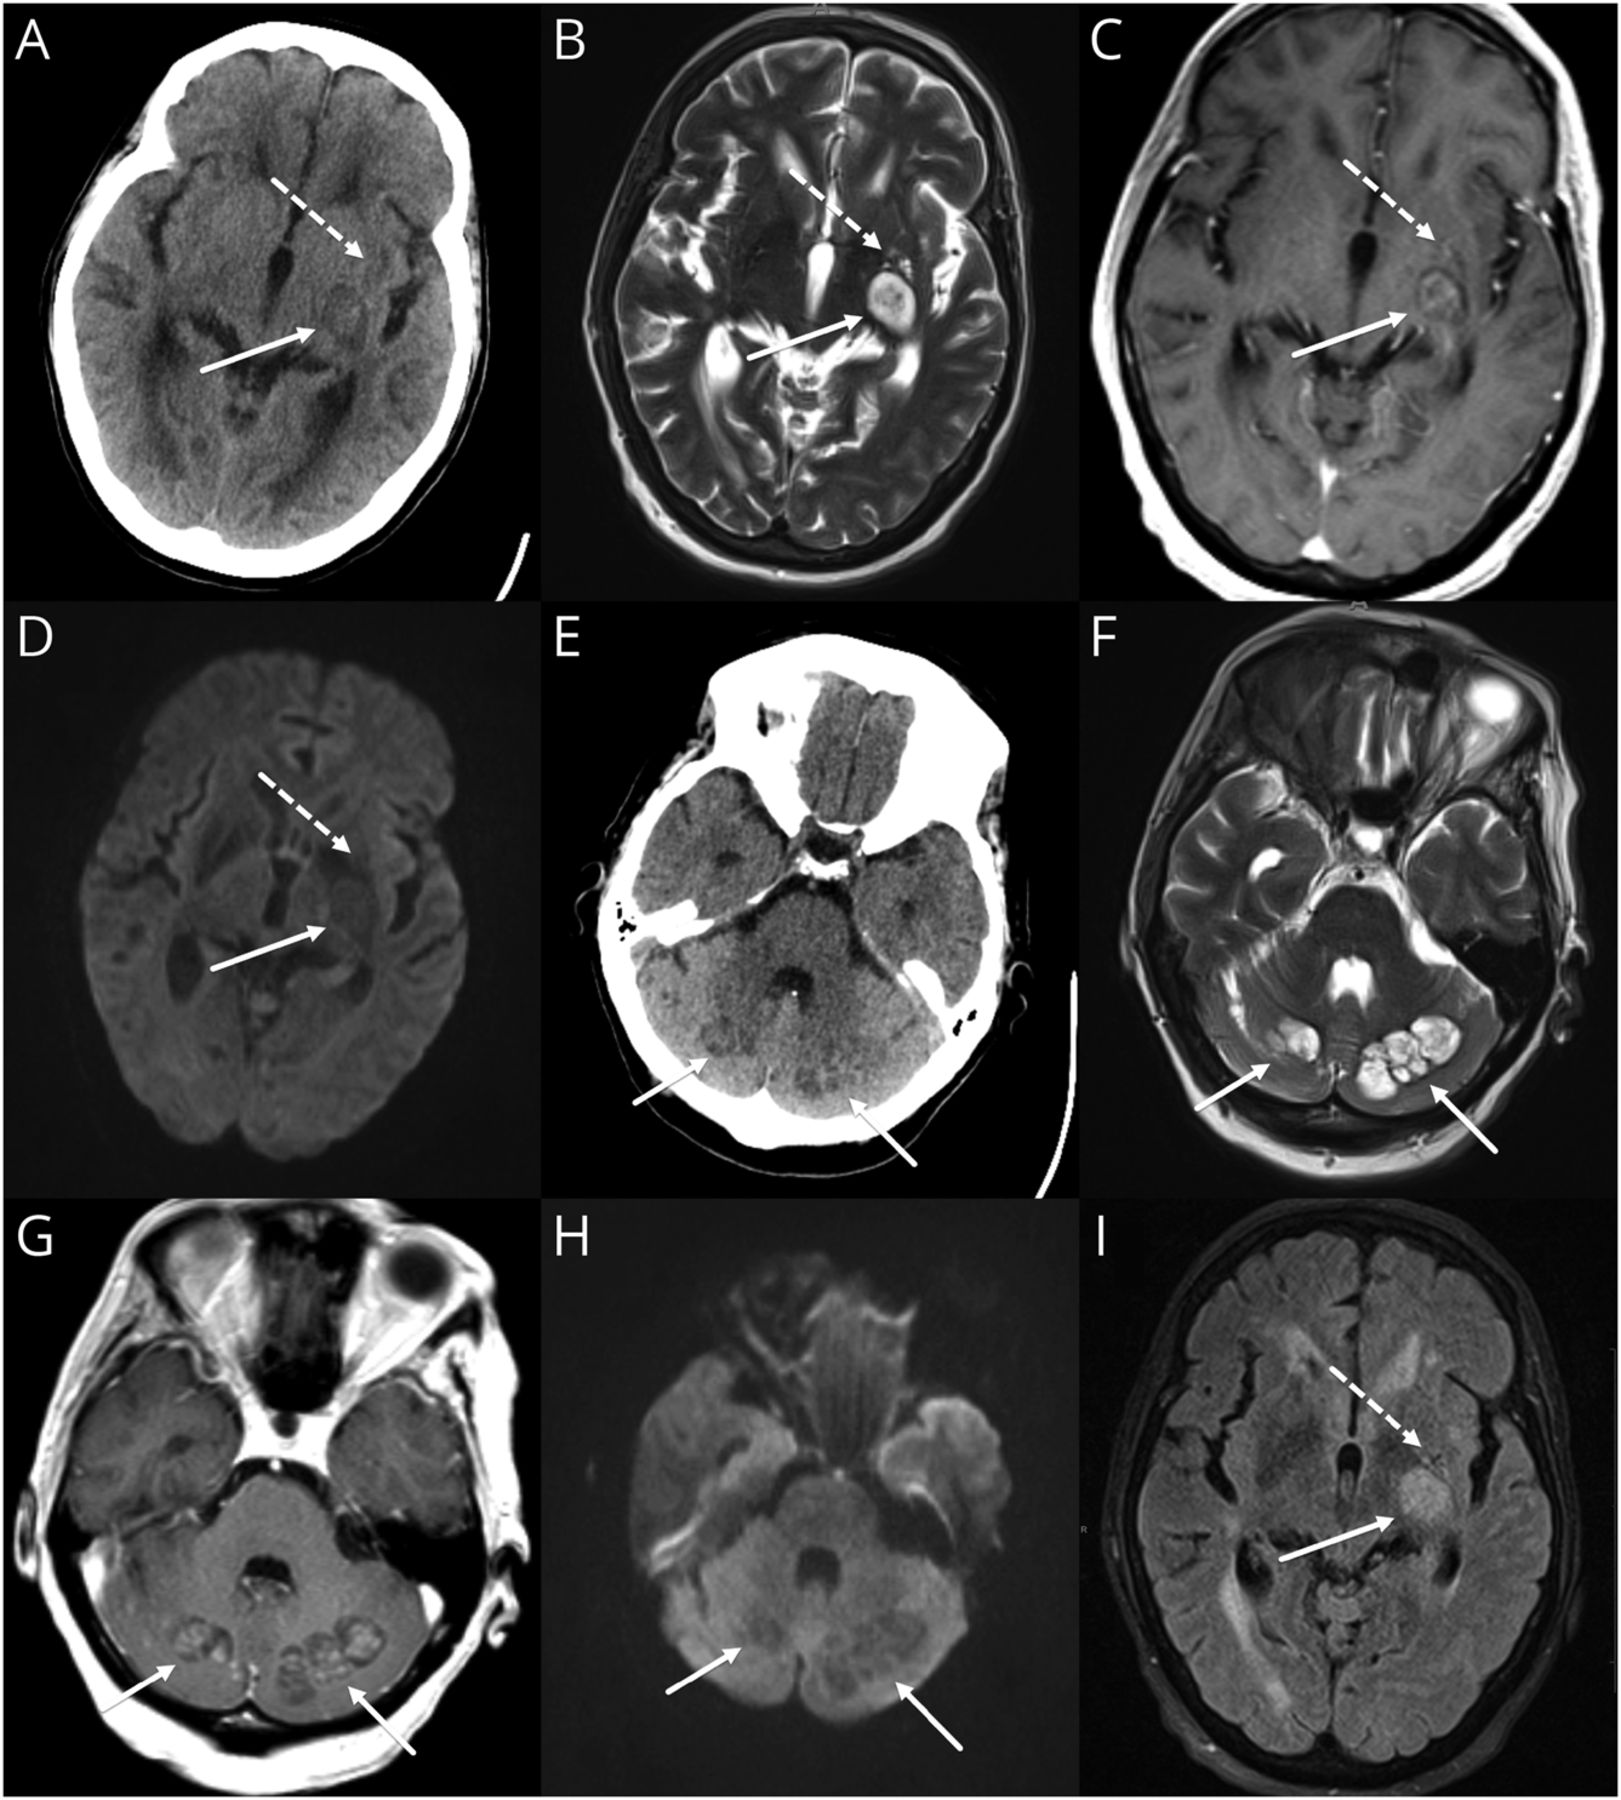

一个66岁的女人从委内瑞拉与糖尿病和无免疫缺陷出现头痛、头晕、下肢无力。Hypodense脑转移病灶在CT的担忧(图A和E),但全身CTs未能揭示主站点。脑磁共振成像(外:我的身材,罪犯)建议颅内cryptococcosus似的质量cerebelli切除,左基底神经节,右颞叶,右枕叶和凝胶状的假性囊肿表现为新扩张的血管周的空间在左侧基底神经节。证实了诊断脑脊液抗原检测。

41 CT (E)、MRI T2 (B和F), postcontrast T1 (C和G),醉酒驾车(D和H), T2天赋(I)大脑的图像。切除(实心箭头)合并感染、出现异构hypodense病变在CT。在MRI上,分“脏”T2是典型的外观与内部增强。相比一个典型的脓肿,没有内部限制扩散。假性囊肿在CT(虚线箭头)是糟糕,出现hypodensity的模糊区域。MRI上表现为新扩张血管周的空间。片状增强postcontrast图像和周围水肿才能区别于正常血管周的空间如果成像之前不可用。醉酒驾车= diffusion-weighted成像;天赋= fluid-attenuated反转恢复。

虽然隐球菌病一直被视为一种疾病的免疫力低下,很少免疫活性的个人可以影响(特别是隐球菌gattii)。成像,3表现可能是:(1)脑膜疾病显示脑膜增强,(2)脑膜疾病扩展到血管周的空间,导致膨胀和囊性区(假性囊肿形成),和(3)感染性材料的聚结到弗兰克实质集合(切除)。金宝搏188手机app1